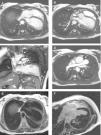

Cardiac MRI images. (A-D) Steady-state free precession images. (A) Axial image showing left and posterior heart displacement. (B) Axial image displaying non-visualization of the pericardium and pericardial fat around the left ventricle (between the white arrows). (C) Coronal image showing absence of the pericardium and pericardial fat around the left ventricle and great vessels (between the white arrows), with lung tissue interposition in the several recesses where the pericardium is usually found. (D) Axial image showing lung tissue in the aorto-pulmonary window (white arrow), which is considered a pathognomonic sign of this condition. (E) T1-weighted axial image with no abnormalities, particularly, fat tissue deposition. (F) Delayed gadolinium-enhanced axial image with no macroscopic areas of myocardial fibrosis/necrosis.